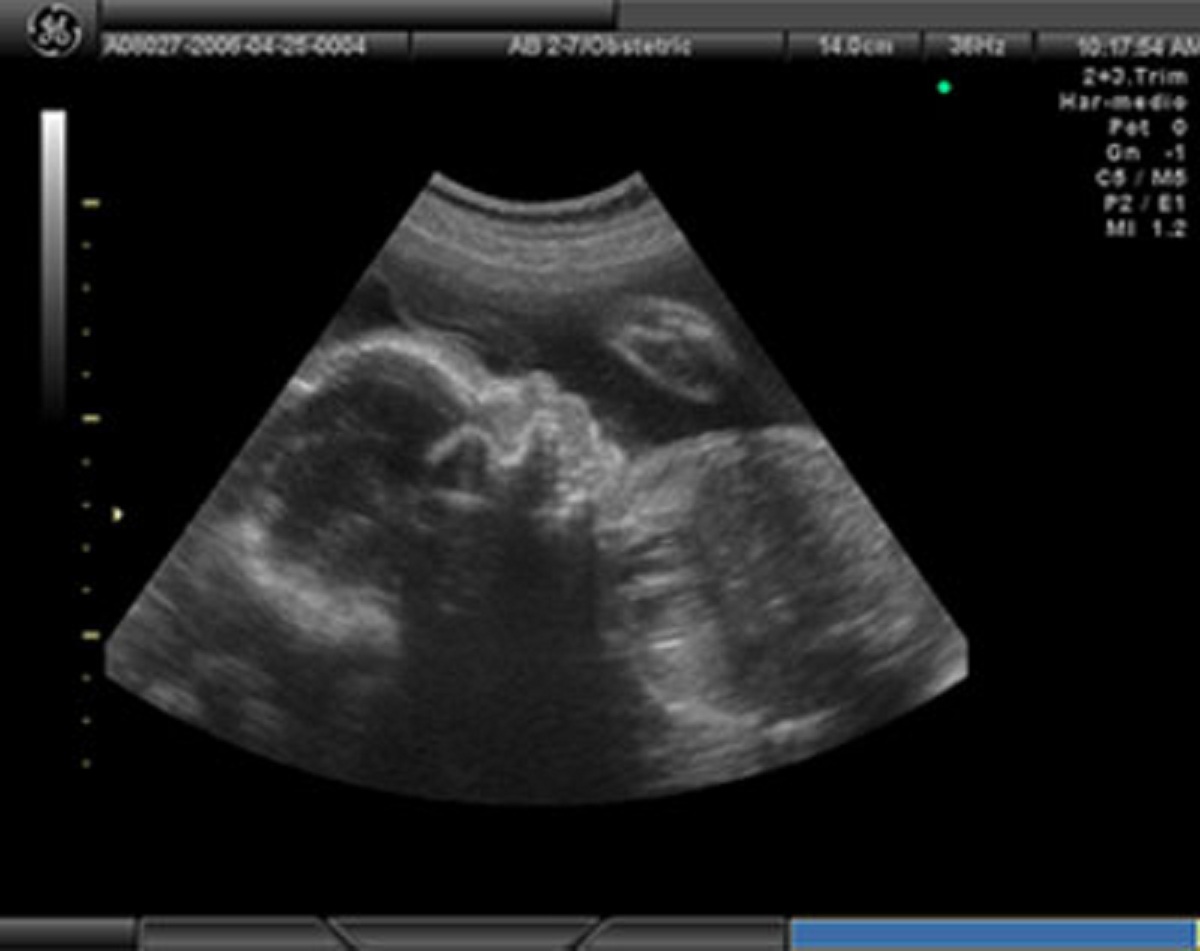

Marian se acostó en la camilla mientras el médico la preparó para auscultar su vientre. En la pantalla se observaba movimiento, se sentían los latidos.

-Allí está tu primogénito. Parece muy intranquilo. Se mueve mucho, es raro. Su corazón late muy aprisa. Extraño...

-Sí, está bien, creo, sólo que quisiera hacer más pruebas, para estar seguro. -El doctor no quiso preocuparla más; algo no marchaba bien en esa pantalla, el feto se movía como si quisiera salir de allí.... – Vuelve en dos semanas para hacerte otros exámenes